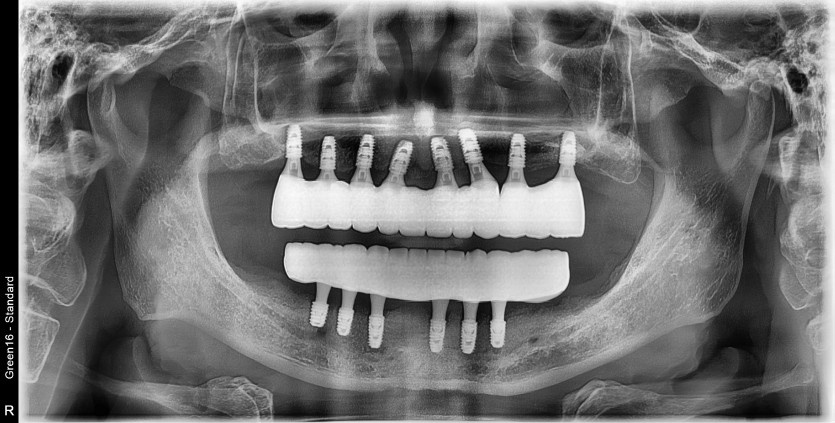

만 61세 전체 임플란트 증례(하악 풀아치)

전체 임플란트 증례입니다.

14개의 임플란트로 완성하였습니다.(하악 풀아치 진행)